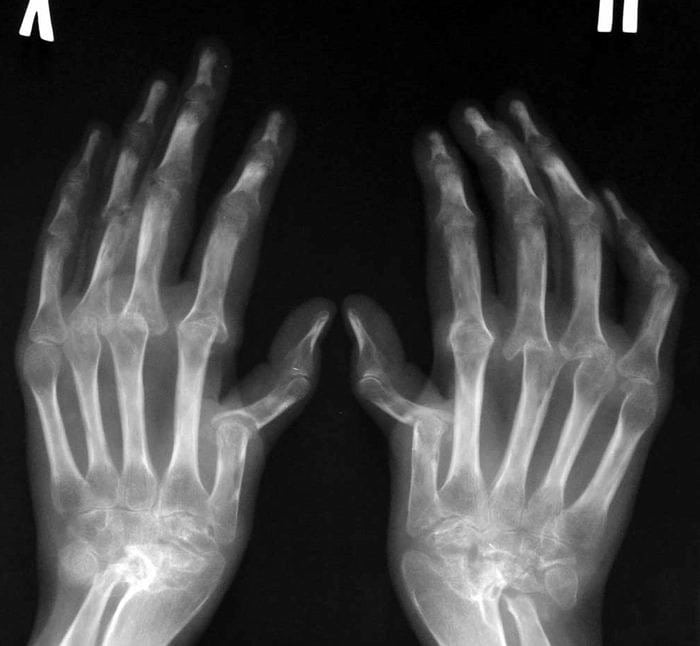

Обнаружить заболевание помогает ряд инструментальных исследований, наиболее информативна рентгенография. На полученных изображениях визуализируются поврежденные костные и хрящевые ткани, сужение суставных щелей, краевые эрозии. С помощью МРТ оценивается состояние связочно-сухожильного аппарата и расположенных рядом с суставом мышц. В лаборатории проводится исследование суставной жидкости для установления неспецифических воспалительных признаков. Окончательно выставить диагноз помогает выявление типичных иммунологических маркеров заболевания: ревматоидного фактора, концентрации Т-лимфацитов, содержание криоглобулинов.

- результаты рентгенографии свидетельствуют о наличии эрозий и декальцификации костных тканей в сочленениях кистей с формированием кист.

Доминирующее значение в постановке диагноза имеют результаты рентгенологического исследования. На полученных изображениях хорошо заметны признаки отечности мягких тканей, околосуставного пятнистого или диффузного остеопороза, кистовидной перестройки костных тканей. При потере костной массы эпифиз пораженного сочленения становится более прозрачным. На рентгенограммах четко просматриваются суженые суставные щели, нечеткие и неровные поверхности гиалиновых хрящей. Если кортикальный слой подвергся значительной деструкции, костные поверхности соприкасаются друг с другом. Если некоторые участки рентгенограмм неинформативны, то назначаются дополнительные инструментальные исследования: